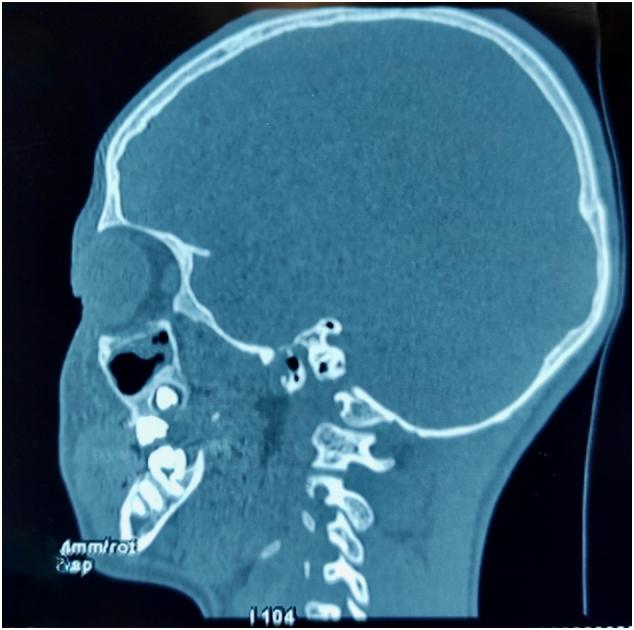

The authors report a ten years-old male child, reported to the oral and maxillofacial surgery department, Ibn Rochd university hospital, Casablanca, Morocco. The child was diagnosed for left orbital floor fracture, complaining of orbital trauma due to road accident. The injury occurred at the left orbit level. There was no general story of any disease.

In more than 40% of all the facial fractures parts of the orbital rim or/and the internal orbit are injured with a variety of fracture patterns. Accurate assessment is required in order to correct any bone defects or displacements. The surgical approaches have become more reduced offering better control of orbital pathological processes. Orbital lesions are precisely localized through imaging. Also, the approach decision depends on location, size and vascularization. No consensus exists regarding the timing of the repair, the repair technique and the optimal implant. In this case presentation, the defect on the orbital floor was extended by mobilization of the fragments. A combination of incisions was necessary due to the change in the dimensions of the defects intraoperatively and entrapment of orbital tissue by the placement of an implant.